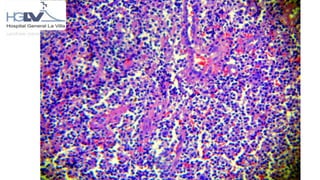

HALLAZGOS MICROSCÓPICOS

REPORTE DEL SERVICIO DE PATOLOGÍA

IMAGEN HISTOLÓGICA COMPATIBLE CON PROLIFERACIÓN

NEOPLÁSICA LINFOIDE.

NOTA: ES INDISPENSABLE REALIZAR TÉCNICAS DE

INMUNOHISTOQUÍMICA PARA CONFIRMAR PROCESO NEOPLÁSICO.

HISTOLOGICAMENTE

Infiltrado linfoide difuso, situado por debajo del epitelio o

epidermis, el infiltrado linfoide está constituido por células

pequeñas tipo centrocito, nidos de células monocitoides,

centroblastos y muchas células plasmáticas. Se observan folículos

con centros germinales o con colonización de los mismos. La lesión

linfoepitelial no se observa en glándula lagrimal pero puede estar

presente en el epitelio ductal.